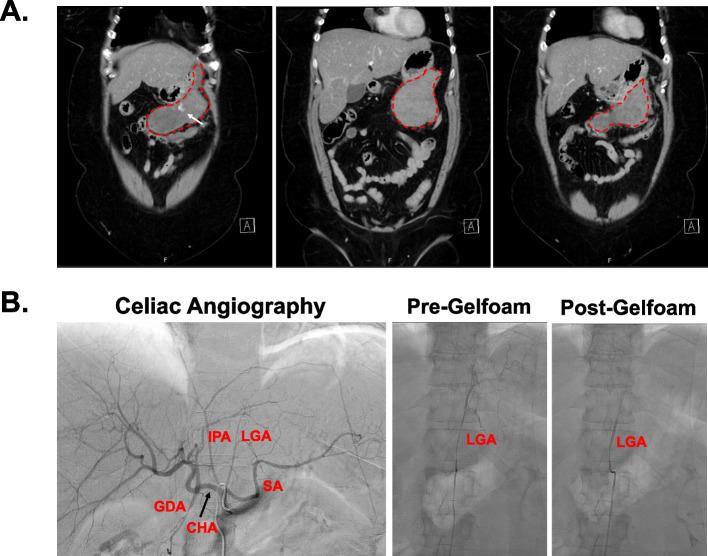

Synovial sarcoma is a rare soft tissue sarcoma which frequently involves the upper or lower extremities. Soft tissue sarcomas including synovial sarcoma have a propensity to metastasize to the lungs, and there are very few reports of metastatic lesions in other locations.Here, we report a case of a 49-year-old patient who underwent neoadjuvant chemoradiation for an upper extremity synovial sarcoma and presented approximately 4 years later with abdominal pain and hemoperitoneum and was ultimately found to have metastatic synovial sarcoma involving the greater curvature of the stomach and surrounding peri-gastric soft tissue. We describe the multidisciplinary management of this complex patient presentation and propose that expanded surveillance imaging beyond that of the local tumor resection bed and the chest may be beneficial especially in tumors with high-risk features.